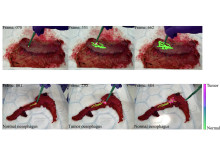

Leading infection experts came together to explore clinical challenges in infection and how Imperial’s interdisciplinary expertise can solve them.